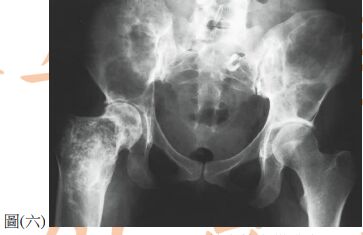

76. 下腹部 X 光雖然不是骨盆腔腫瘤的主要診斷方式,但仍然可以提供一些線索幫助診斷。圖(六)為腹部X光,可見到一個骨盆腔鈣化的組織。下列相關鑑別診斷,何者可能性最高? (A) 畸胎瘤(teratoma ) (B) 輸卵管卵巢膿瘍(tubo - ovarian abscess) (C) 黃體囊腫(luteal cyst) (D) 輸卵管水腫( hydrosalpinx )